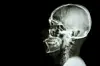

En MR- eller CT-scanning afslører oftest hjernetumorer. (Foto: Shutterstock)

Hvis det bliver mistænkt, at man kan have en hjernetumor vil man blive henvist til en CT- eller MR-scanning. En CT-scanning, hvis mistanken går på noget andet end en hjernetumor – en MR-scanning, hvis mistanken går på en hjernetumor. Undersøgelserne vil kunne give tydelige billeder af hjernevævet, så en tumor vil kunne ses.